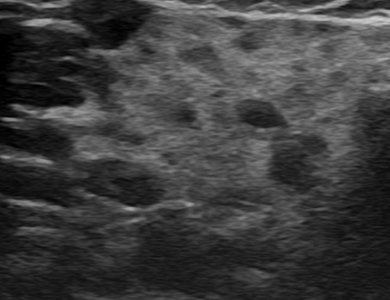

¿ìÃø °æºÎ ¸²ÇÁÀý

img

ÁÂÃø ÀÛÀº »ó¼± ¾Ï